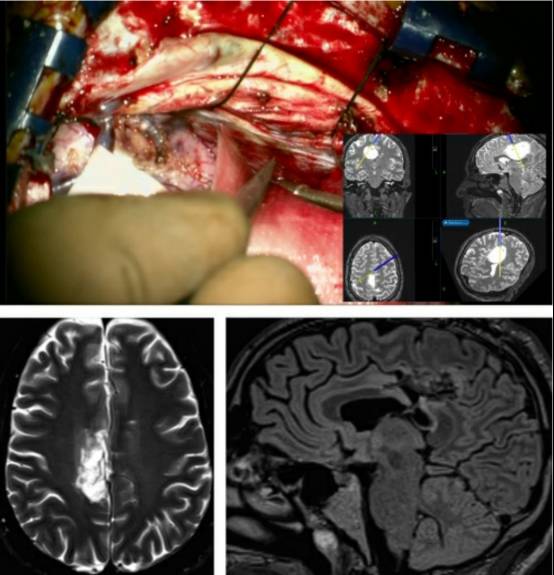

病例2:男性,35岁,表现为顽固性癫痫。

图7. 术前影像学提示为低级别胶质瘤,位于右侧脑室周围并扩展至额叶内侧。中间一列的上图(冠状位)和下图(矢状位)fMRI提示肿瘤位于感觉运动功能区。扩散张量成像(DTI)(右上图)显示肿瘤推挤运动功能纤维束移位。

为了避免过度牵拉同侧功能区,到达肿瘤外侧缘,笔者使用经对侧纵裂入路切开大脑镰技术安全切除肿瘤。

图8. 经大脑镰入路手术角度(最上图)。笔者使用脑皮层刺激定位额叶内侧至肿瘤前部功能区。使用皮层下功能区定位和经大脑镰“斜线”入路切除肿瘤。术后影像提示占位完全切除(底下图)。